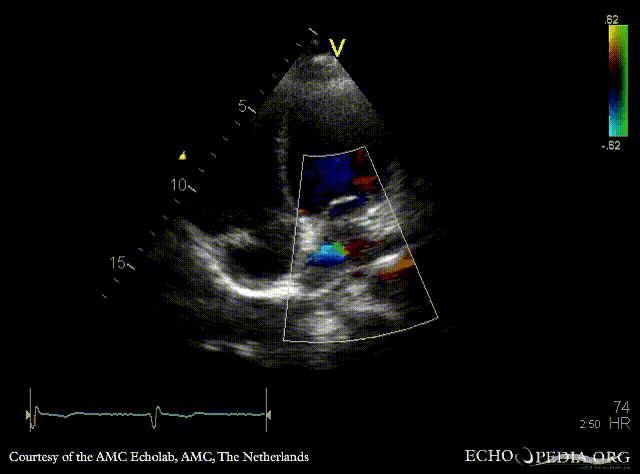

Abnormal pulmonary vein drainage

Pulsed-wave signal of pulmonary veins flow PSAX: dilated coronary sinus